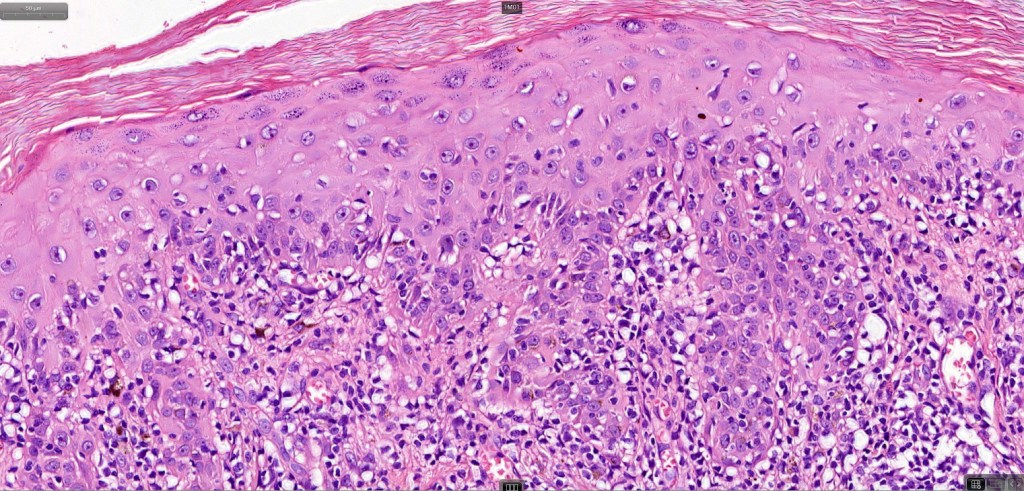

•Hyperkeratosis +/- parakeratosis

•Wedge-shaped hypergranulosis

•Generally irregular (sometimes saw-tooth) acanthosis but may show broad acanthosis

•Interface change

•Conspicuous cytoid bodies

•Pigment incontinence

•Band-like or perivascular infiltrate of lymphocytes, histiocytes with occasional eosinophils & plasma cells